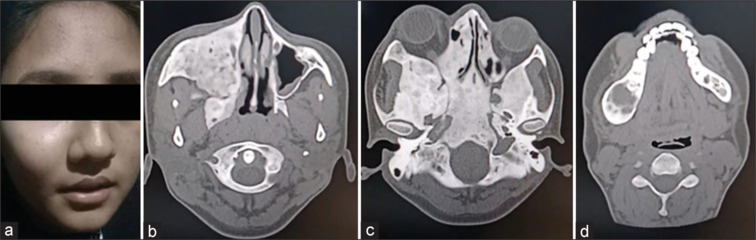

McCune-Albright syndrome is a rare and challenging disorder characterized by a triad of cutaneous, bone and multiple endocrine abnormalities. We present the case of a 15-year-old female with varied symptoms including precocious puberty, prolactinoma, polyostotic fibrous dysplasia, and hyperthyroidism. On examination, she had a palpable nodule in the right lobe of the thyroid with an atrophic left lobe on ultrasonography. Thyroid scan in this patient posed a diagnostic challenge which was resolved with additional single-photon emission computed tomography/computed tomography (SPECT/CT). On SPECT/CT, she was diagnosed with autonomously functioning thyroid nodule and treated with 15 mCi of 131I.